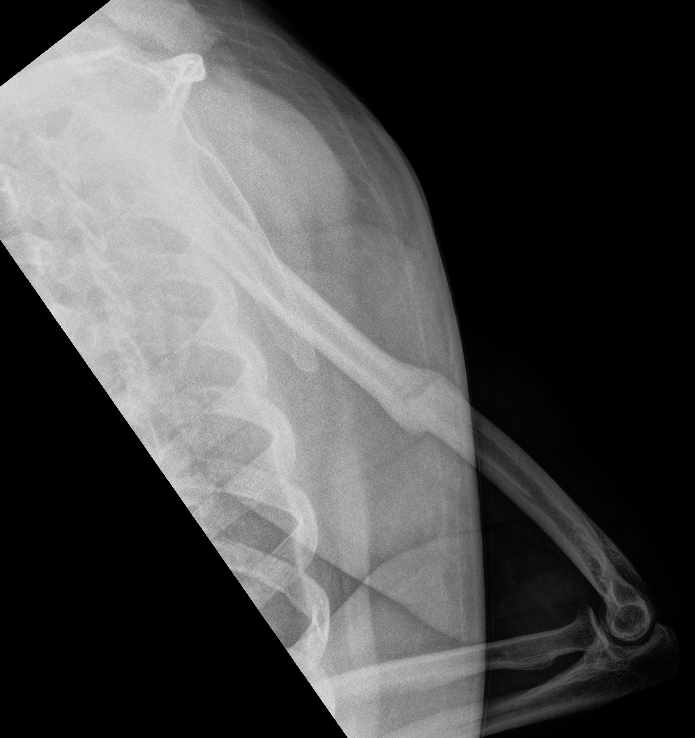

Holstein Lewis fracture

Holstein Lewis fractureHolstein Lewis

Holstein-Lewis JBJS Am 1963

- series of 7 oblique distal third fractures with radial nerve injury

- all were treated operatively

- nerve in fracture gap in 2 / impaled in 1 / severed in 2 / contused +/- in callus in 2

- advised against attempted closed reduction

- risk of contusing nerve between fragments

- advised early open reduction through anterolateral approach

- the radial nerve is closely assoicated with the fracture site and the fracture spike